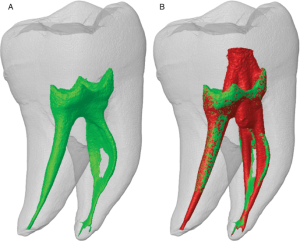

Image analysis is a critical component of clinical and preclinical imaging research, providing a means of quantifying and interpreting the data generated by imaging modalities such as PET, SPECT, and CT. In clinical imaging, image analysis is used to aid in diagnosis and treatment planning. For example, in oncology, image analysis can be used to assess the response to chemotherapy and radiation therapy, providing a means of monitoring the effectiveness of treatment and making adjustments as necessary.

The same image analysis techniques can be applied to both clinical and preclinical images, allowing for a seamless transition between research modalities. Moreover, image analysis has additional applications in clinical research, beyond the evaluation of disease progression or response to therapy. For example, image analysis can be used for radiation treatment planning to optimize the radiation dose and minimize side effects.

At our company, we provide a wide range of image analysis services for both preclinical and clinical imaging research. Our team of experts has extensive experience in conducting image analysis for various modalities, including PET, SPECT, CT, and optical imaging. We offer a comprehensive set of services, such as image registration, segmentation, quantification, and statistical analysis. We understand the importance of accurate and precise image analysis in the success of research projects, and we use state-of-the-art software and techniques to deliver reliable and reproducible results.